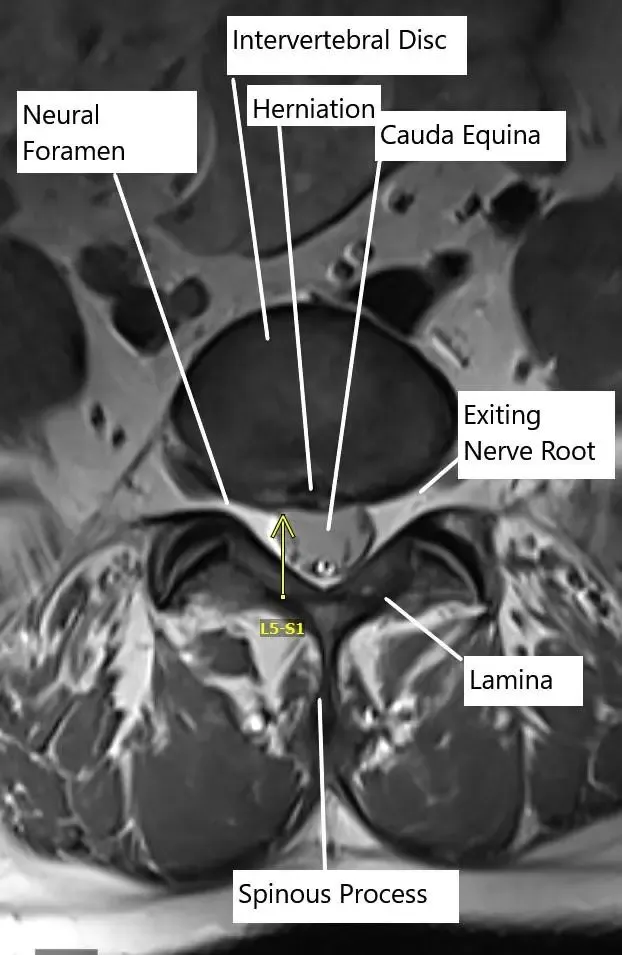

Axial section of the spine showing central disc herniation.

By Location:

- Central: Compresses spinal cord or cauda equina.

- Paracentral: Most common; affects descending nerve roots.

- Foraminal or far lateral: Compresses exiting nerve roots.